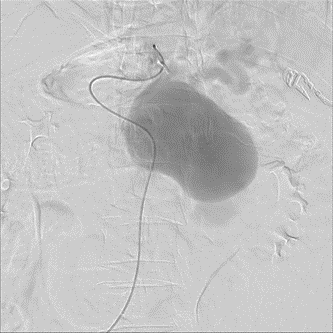

手术过程(一):经股动脉超选脾动脉造影,可见巨大脾动脉瘤,下后方破裂可能

图片

手术过程(二):使用Ⅱ型AVP栓塞载瘤动脉远端,弹簧圈栓塞脾动脉瘤瘤体,但瘤体巨大,弹簧圈略显不足